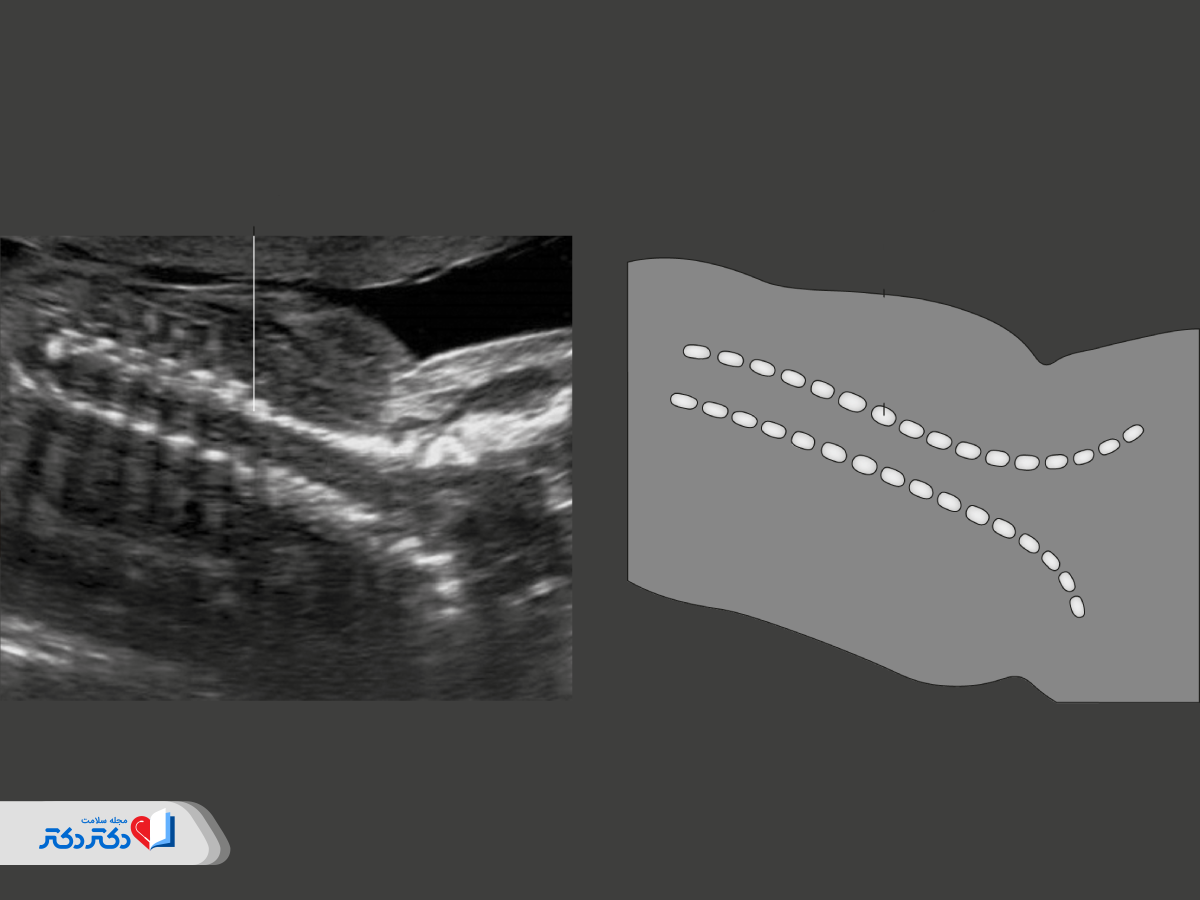

ستون فقرات

اصلیترین ناهنجاریهای اسکلتی و ستون فقرات در سونوگرافی آنومالی قابل مشاهده هستند؛ بنابراین ستون فقرات جنین از نمایی نزدیک و بهصورت مقطعی از نظر موارد زیر بررسی میشود:

- تراز بودن مهرهها (قرارگرفتن مهرهها در یکراستا)؛

- پوشش کامل ستون فقرات با پوست در پشت جنین؛

- شکل و وضعیت رشد استخوانها و مهرهها؛

- نحوه بستهشدن ستون فقرات جنین.

پزشک متخصص علاوهبر اطمینان از سلامت ستون فقرات، بهدنبال ناهنجاریهایی مانند انحراف یا نقص در ستون فقرات نیز میگردد. چون هر کدام از این موارد نشاندهنده ابتلا به بیماریهای مادرزادی یا اختلالات عصبی است.